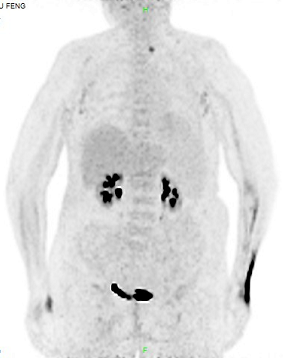

患者10月余前无明显诱因出现全身皮疹,弥漫性潮红,伴瘙痒,无发热,自行外用药治疗(具体不详)稍好转。10月来全身皮疹伴瘙痒反复出现,多次外院就诊,予抗过敏治疗(具体不详)无明显缓解。50余天前患者出现畏寒发热,体温最高39.5℃,无咳嗽

抗感染等治疗仍反复发热,全身皮疹伴瘙痒、脱屑(见图1),为进一步诊治来我院就诊,拟“发热待查”收住入院。

图1

查体:P 106次/分,R 20次/分,BP 154/73mmHg,T 37.5℃。神志清,精神软,全身皮肤潮红、肿胀、脱屑,颈部、腋下、腹股沟可及肿大淋巴结,约黄豆大小,可滑动,无触痛。双肺呼吸音粗,可闻及少许啰音,心律齐,各瓣膜区未闻及病理性杂音,腹软,无压痛及反跳痛

,肝脾肋下未及,双下肢轻度浮肿,左侧腹股沟淋巴结活检伤口未愈合,无明显渗液。